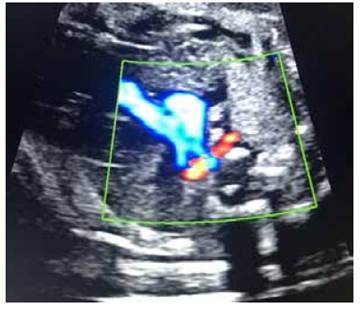

At 33 weeks the fetus showed cephalic presentation by ultrasound, with normal growth, normal levels of amniotic fluid, regular fetal movements. Fetal echocardiogram showed the ARSA and no other cardiac or extracardiac structural pathology. Doppler of the umbilical artery revealed a normal pulsatility index. Figure 3.